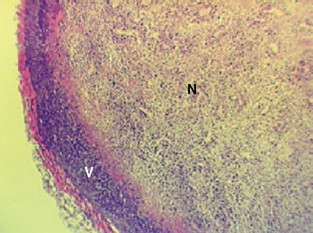

Typical example of a tumour with a viable rim (V) and central necrosis (N) following exposure to a vascular disrupting agent.